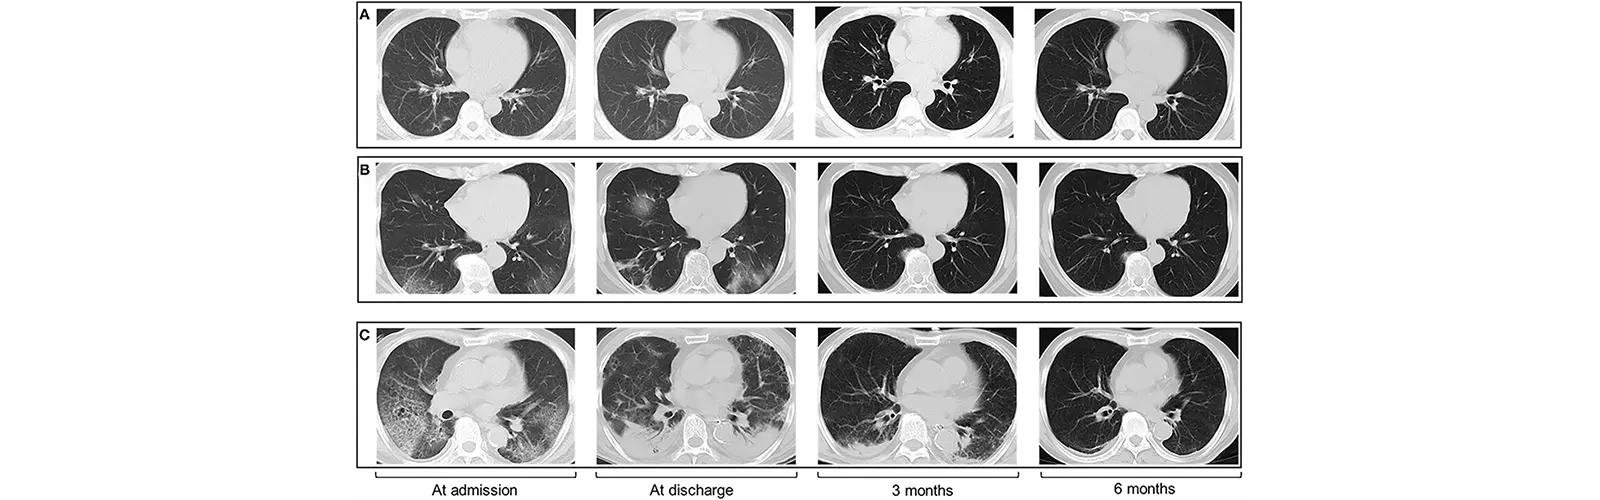

HRCT (High-Resolution Computed Tomography) Chest plays an important role in cancer detection, particularly in the diagnosis and staging of lung cancer. HRCT is a type of CT scan that uses special techniques to produce detailed, high-quality images of the lungs and other organs.

In lung cancer, HRCT can detect early-stage tumors and help distinguish between benign and malignant nodules. It can also help determine the size and location of the tumor, as well as whether it has spread to nearby lymph nodes or other organs.